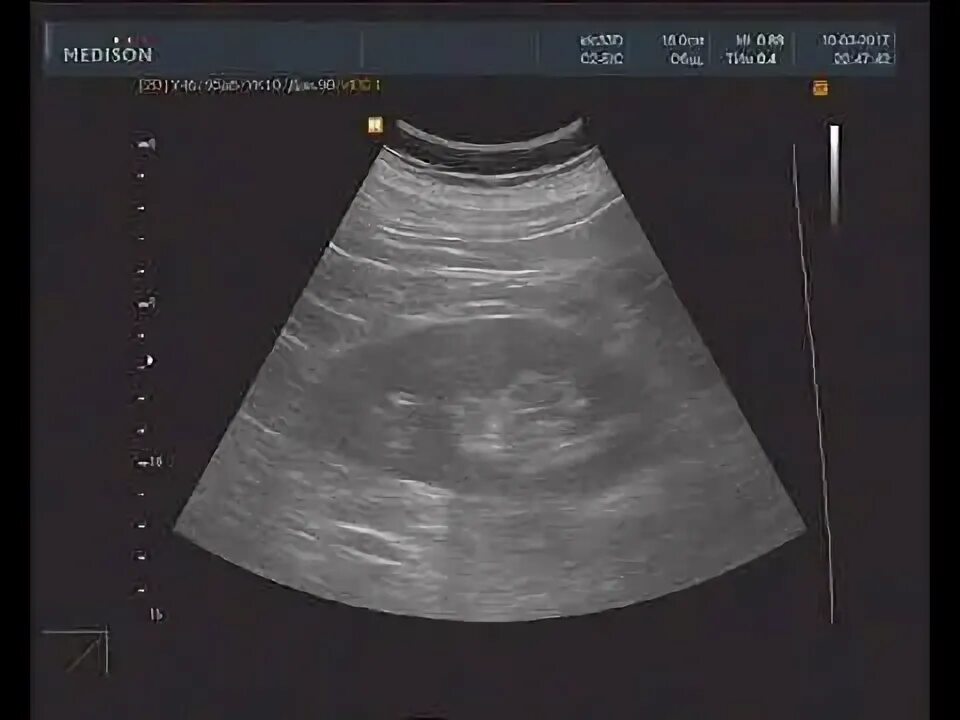

Нефросклероз почек на узи что это такое